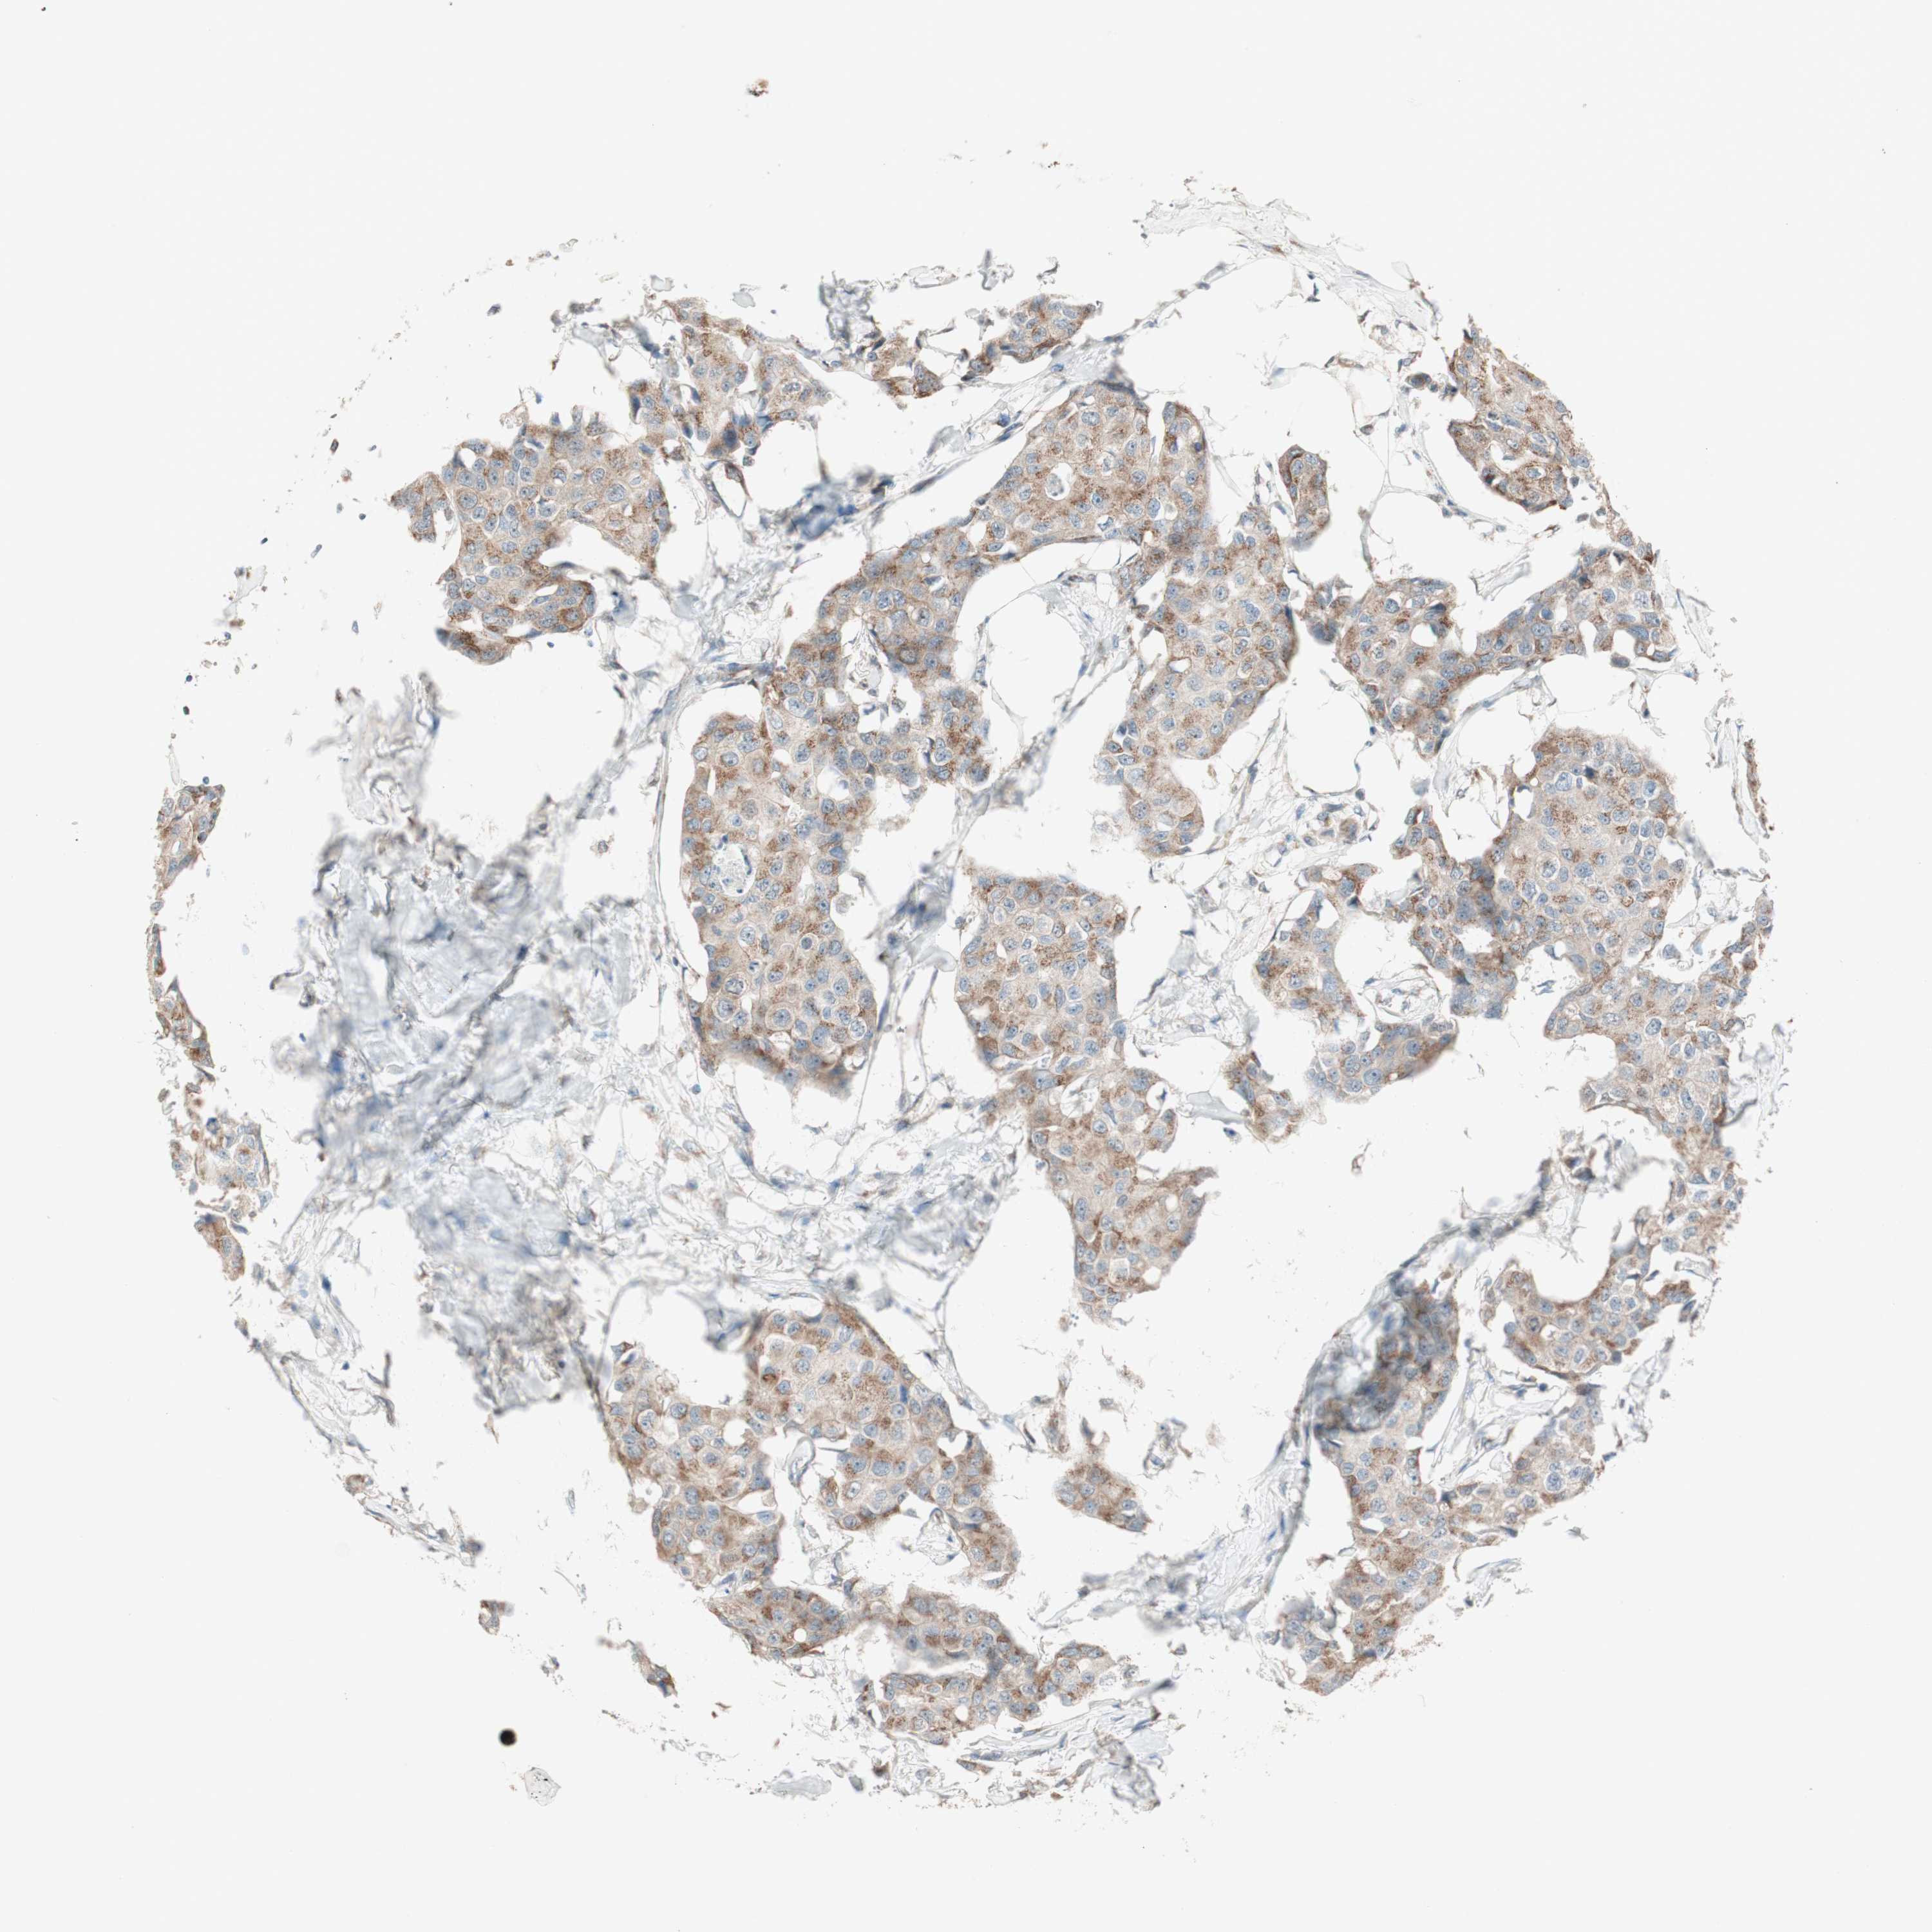

CANCER BREAST CANCER Show tissue menu

BRCA TCGA BRCA VALIDATION PROTEIN EXPRESSION

Breast cancer

Human cancer

SEC16A is not prognostic in Breast Invasive Carcinoma (TCGA)